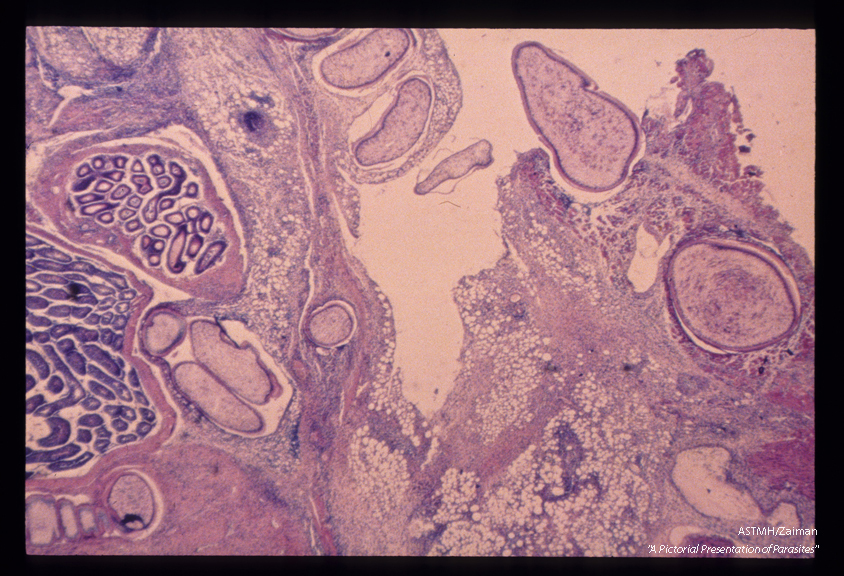

Experimental sparganum infection in a rat. Multiple sections of the parasite are seen within the rat tissues.

Spirometra mansonoides

Description: Experimental sparganum infection in a rat. Multiple sections of the parasite are seen within the rat tissues.